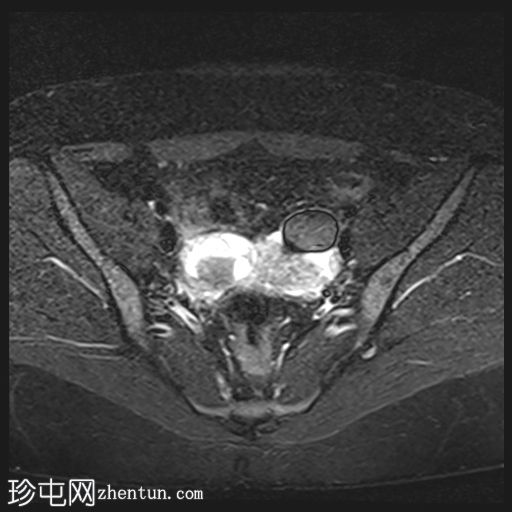

轴位

T2加权像

双侧卵巢位置接近(卵巢相吻),左侧卵巢内可见一边界清晰的囊性病变,大小约3.1 × 2.7 × 2.9 cm,T1加权像呈高信号,T2加权像可见暗点征及内部暗点征。以上MRI特征符合卵巢子宫内膜异位囊肿的诊断。

右侧卵巢可见一囊肿,大小约为 2.8 × 2.0 × 2.2 cm,T1 加权像呈高信号,囊内可见液-液平面,提示囊内含有不同时期的出血性物质。由于对侧卵巢存在典型的子宫内膜异位囊肿,且该囊肿无强化,影像学表现强烈提示为另一子宫内膜异位囊肿。

双侧卵巢均可见多个小卵泡。